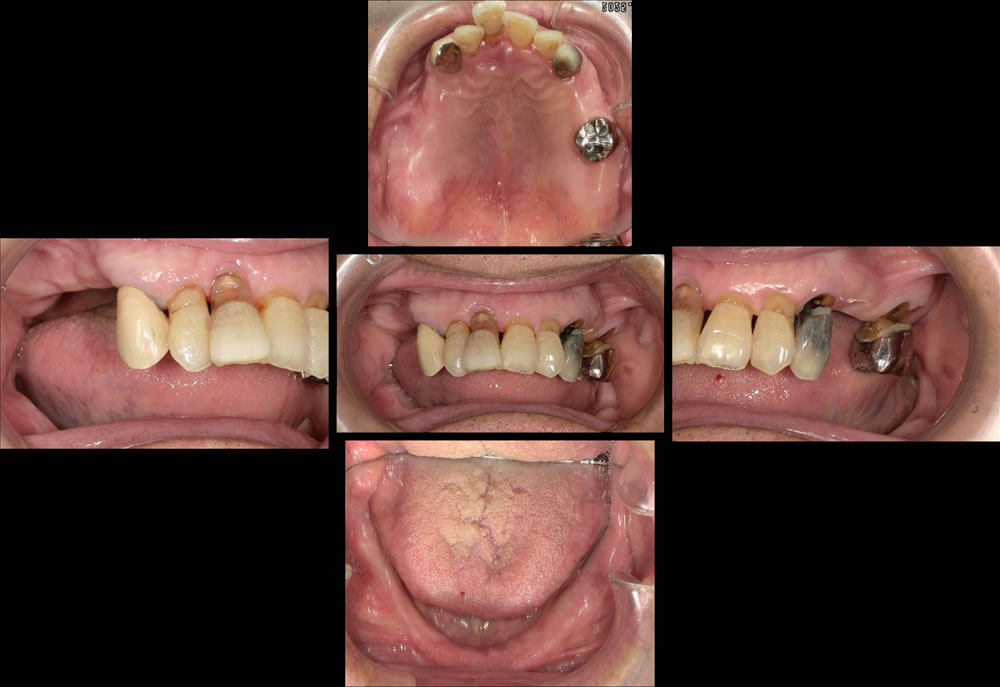

コピーデンチャーを用いて下顎総義歯を作り変えた症例

こちらの患者さまは、他院で総義歯を作製したものの「噛めない」「外れやすい」という状態が続き、入れ歯の作り直しを希望され来院されました。特に下顎の義歯が安定せず、日常生活にも支障が出ていたとのことです。

初診時のお口の状態

診察したところ、下顎の顎堤吸収(入れ歯を支える歯槽骨が痩せてしまう状態)が進行し、顎の骨の高さが全体的に低くなっていました。このような顎堤の形態では、通常の総義歯は吸着が得られにくく、義歯の安定が非常に難しい症例となります。